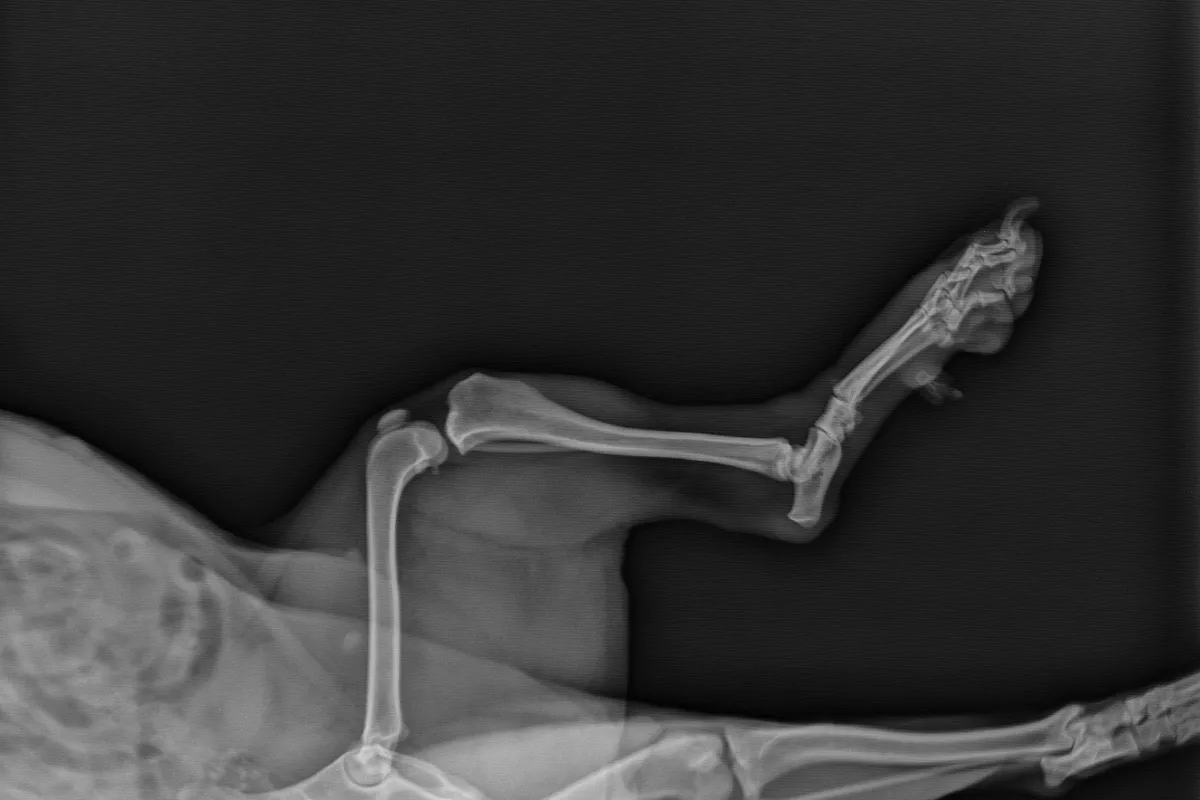

Um einen genaueren Blick auf die Lage der Kniescheibe und umliegende Strukturen werfen zu können, führt Ihr Tierarzt anschließend eine Röntgenuntersuchung durch. Diese trägt außerdem dazu bei, den Winkel der Luxation bestimmen zu können.

Ein Röntgenbild eines Hundes mit Blick auf das linke (oben) und rechte Knie (unten).